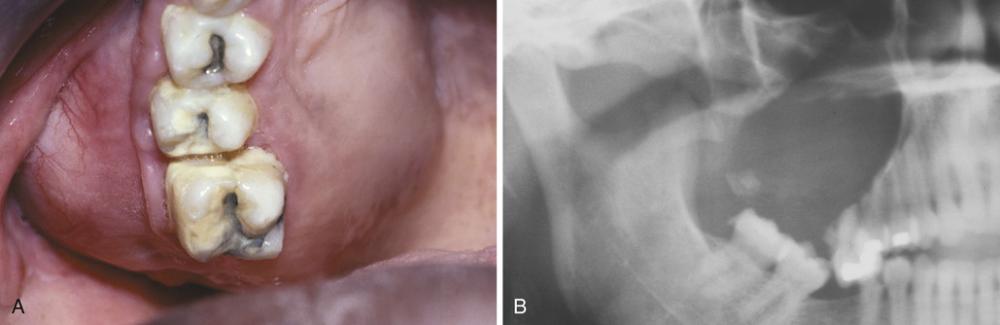

Clinical Features

- develops on buccal of mandibular first or second molar

- occurs in children from 5 to 13 years of age

- slight-to-moderate tenderness

- swelling and foul-tasting discharge

- pocket formation on the buccal aspect

Radiographic Features

- well-circumscribed unilocular radiolucency

- involves buccal bifurcation and root area

- average size is 1.2 cm, but may be up to 2.5 cm

- root apices tipped toward lingual mandibular cortex

Well-circumscribed unilocular radiolucency superimposed on the roots of the mandibular first permanent molar. Periodontal probing revealed pocket formation on the buccal aspect.

buccal bifurcation cyst

Axial computed tomography (CT) image showing a circumscribed radiolucency buccal to the roots of the mandibular first molar, which are tipping toward the lingual mandibular cortex.